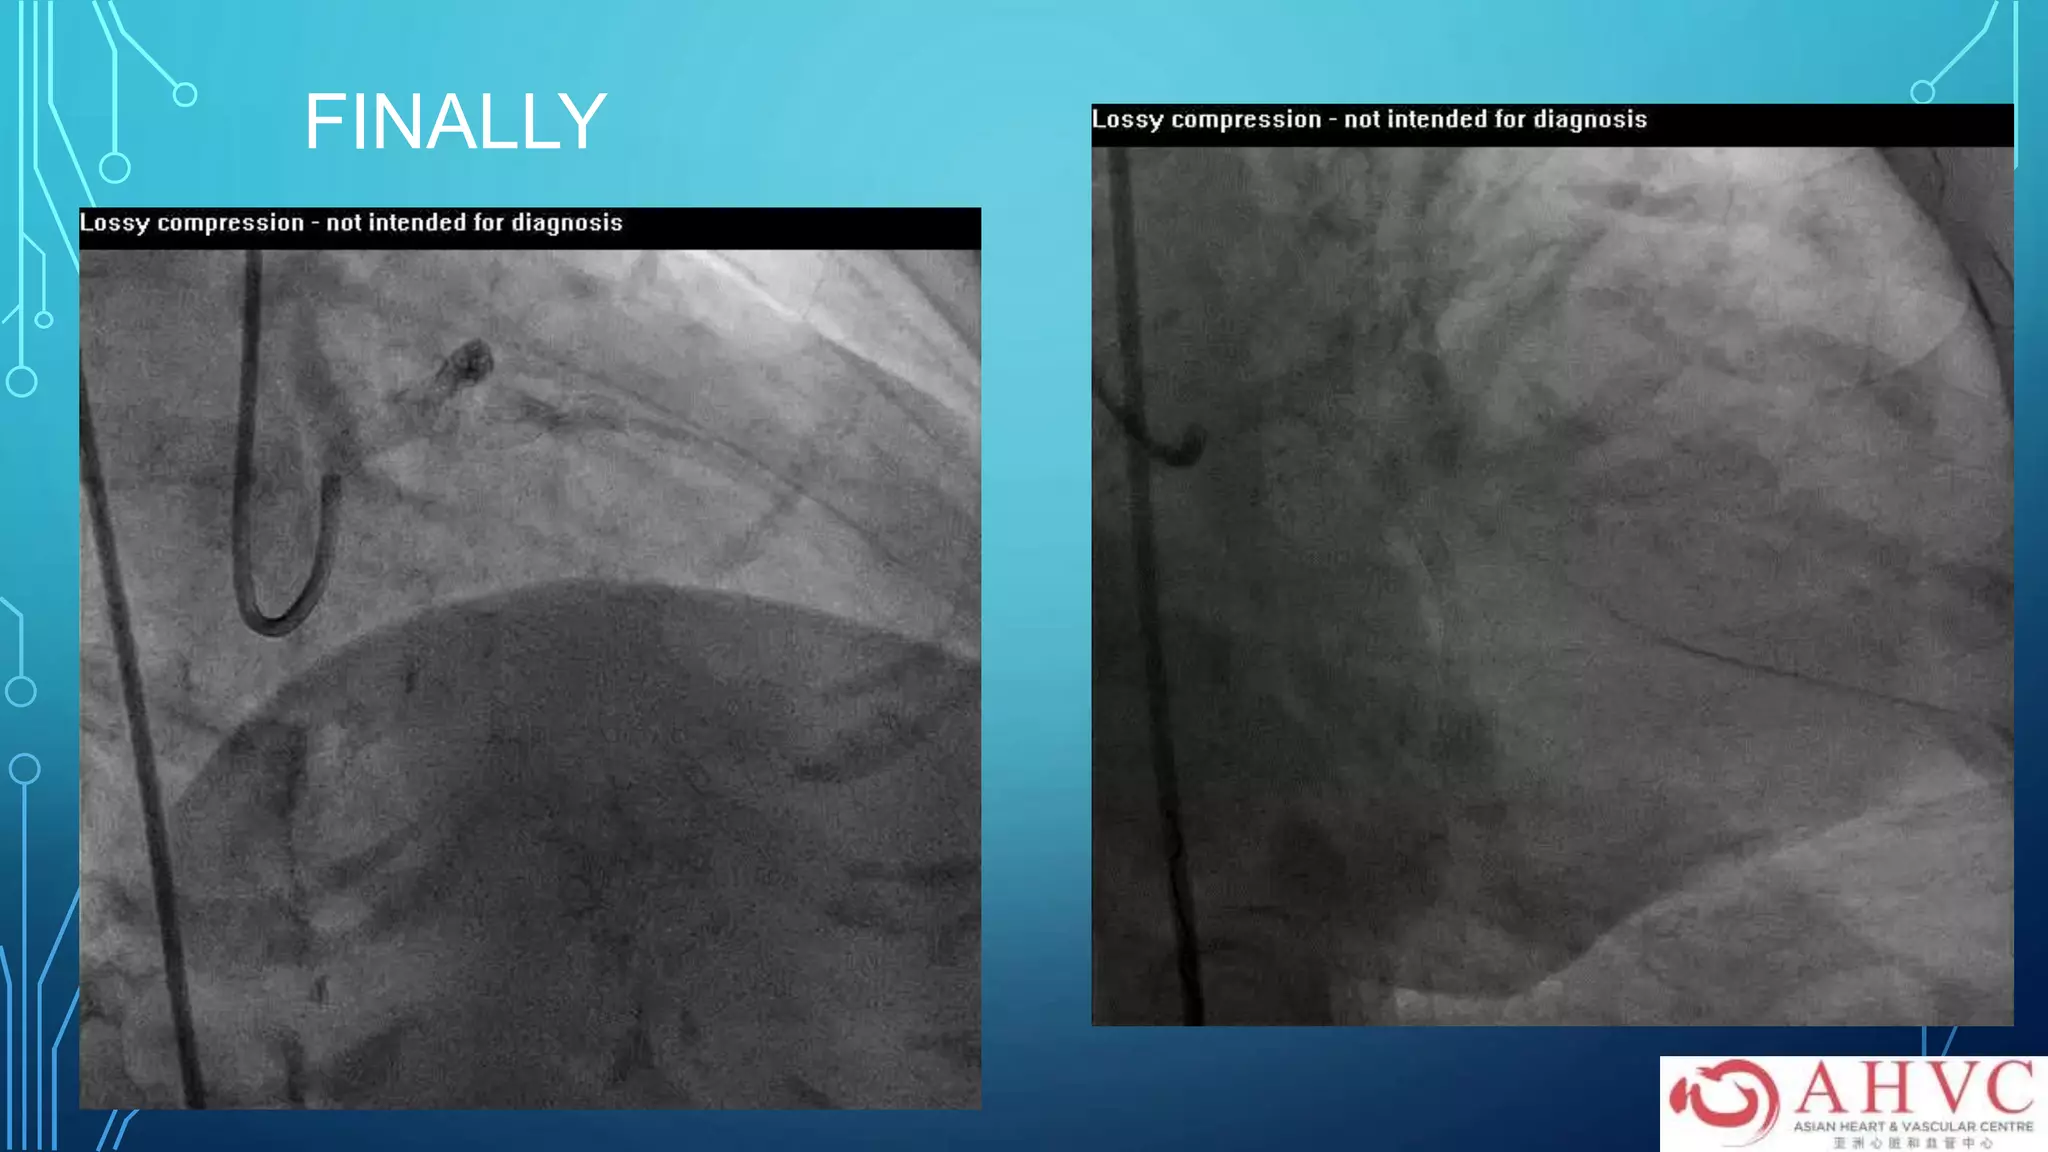

FINALLY

CONCLUSION

•LM stenting in the non-urgent setting is safe

and has low MACE rate at 3 years

•Needs to be done in experienced hands

•Use of IVUS is strongly advocated

•It is a viable alternative to CABG